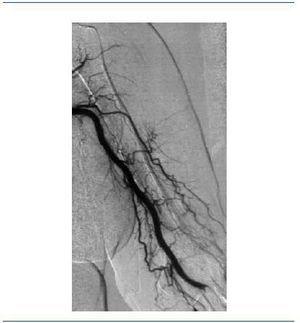

Acude a su sesión de hemodiálisis habitual el 19 de junio de 2007, y a falta de 1,15 h del final (de un total de 4 de diálisis) y habiendo transcurrido toda ella con absoluta normalidad, tras notar una sensación de latido en la FAV, presenta un aumento brusco de la presión arterial y posteriormente de la presión venosa, a pesar de lavados y de una segunda dosis de enoxaparina de 20 mg. Se ausculta la FAV, que no presenta ni soplo ni thrill, con el diagnóstico clínico de trombosis de FAV. Se desconecta a la paciente y se remite al hospital de referencia para intento de trombólisis. A su llegada se realiza analítica, destacando una hemoglobina de 13,1, hematocrito de 38,6% y plaquetas 137.000/mm3. Se realiza asimismo un electrocardiograma (ECG), detectando una arritmia completa por fibrilación auricular, con frecuencia de alrededor de 80 latidos por minuto. En el centro hospitalario proceden al implante de un catéter femoral provisional el 21 de junio de 2007 para poder dializarla, realizando ese mismo día una fistulografía mediante punción de la arteria humeral izquierda; en ella aprecian signos de probable embolismo arterial (figura 1), por lo que se indica el tratamiento con perfusión de 80.000 UI de urocinasa durante 24 horas. En el control posterior se objetiva una repermeabilización de la FAV, con presencia de dilataciones aneurismáticas y trombos en la vena de retorno, así como algún defecto de repleción en la arteria distal (figura 2). El 23 de junio de 2007, ante la resolución del embolismo de la FAV, y tras comprobar su buen funcionamiento al dializarse a través de ésta, se procede a la retirada del catéter femoral.

Figura 1. Obstrucción de la rama arterial de la fístula arteriovenosa